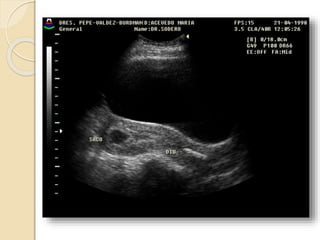

Quistes Funcionales

Quistes foliculares:

Resultan de una falla en la involución.

El folículo se distiende y mide mas de

30mm de diámetro. No dan síntoma a

menos que adquieran mucho tamaño y

sufran ruptura, torsión o hemorragia

Cuerpo lúteo quístico:

Esta dado por una hemorragia exagerada

en un folículo que ovuló y esta en etapa de

regresión.

Frecuentemente son asintomáticos.

Ambos quistes funcionales se resuelven en

dos o tres ciclos.